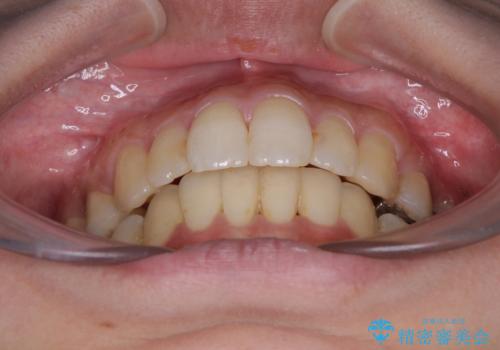

後戻りで突出した前歯をインビザラインで解消

- 抜歯矯正の後戻りで前歯が突出してきていることを気にして来院された患者様です。

口元の突出感を改善するにあたり、抜歯矯正は行うことができないため、奥歯の後方移動とIPR(歯と歯の間を削る)により達成することとしました。

再度後戻りしたときに対応しやすいよう、インビザラインにて矯正治療を行うこととしました。

舌の突出癖がなかなか改善できず、IPRによる前歯の隙間が閉じきらずに、予定よりも長い治療期間となりました。